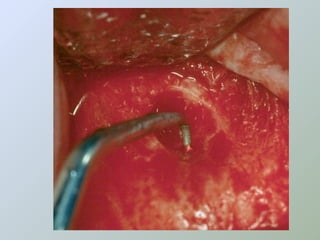

curetagem

• Evitar danos aos dentes

adjacentes

• Procurar remover a totalidade da

lesão

• Porção retro-radicular

• Uso de agentes hemostáticos

Ressecção do

ápice radicular

- apicectomia -

apicectomia

• Acesso ao canal para

exame e inserção de

material obturador

• Para remover uma porção

não debridada/obturada

da raiz